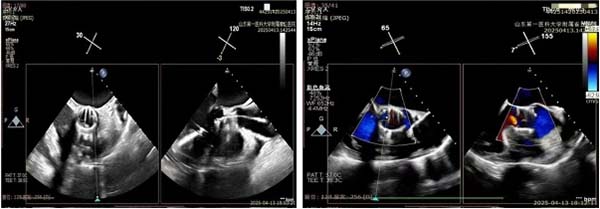

手术当天,杨麟、曹国威团队严密监测循环与呼吸参数,确保麻醉平稳。朱梅实时解读瓣膜解剖与反流评估,为操作提供精确导航。术中,在王安彪指导下,谭琦先经左胸小切口建立心尖通路,送入二尖瓣夹合器,通过TEE引导,精准定位于后叶反流最重区域,首次夹合即见强回声信号,瓣叶开放良好且无狭窄,仅存轻度残余反流,于是,在高难度操作下再次植入第二枚夹合器,完全消除了受累区的反流信号。经过短暂观察后,如术前手术团队所预期,在解决患者二尖瓣反流的问题后,患者左心室负担加重,主动脉瓣反流量增加至重度。

随后,团队迅速转换至TAVR程序。王安彪与朱梅配合,将瓣膜装载并引导至主动脉根部,通过TEE确认瓣环定位无误后,平稳释放瓣膜。超声即时显示人工瓣架固定牢靠,瓣叶开启顺畅,瓣周无间隙回声;多普勒测得瓣区最高流速225 cm/s,圧差20 mmHg,提示置换效果优异。